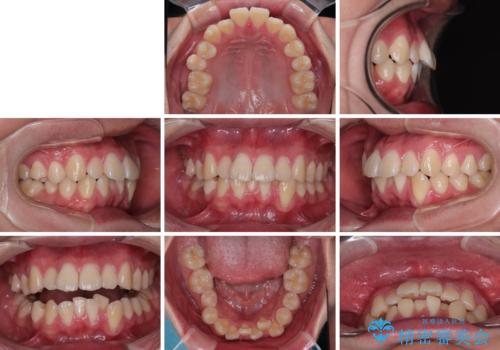

全体的なデコボコをスッキリと ワイヤー装置での抜歯矯正

- 全顎的なデコボコを気にして来院された患者様です。

特に前歯のデコボコが顕著であり、上下左右第一小臼歯の4本を抜歯し、ワイヤー装置を使用して咬み合わせ高さを改善しながら、歯列を整えて行くこととしました。

移動が順調に進み、1年半の短期間で治療を終えることができました。

前方に突出した上顎前歯の傾斜も改善されました。